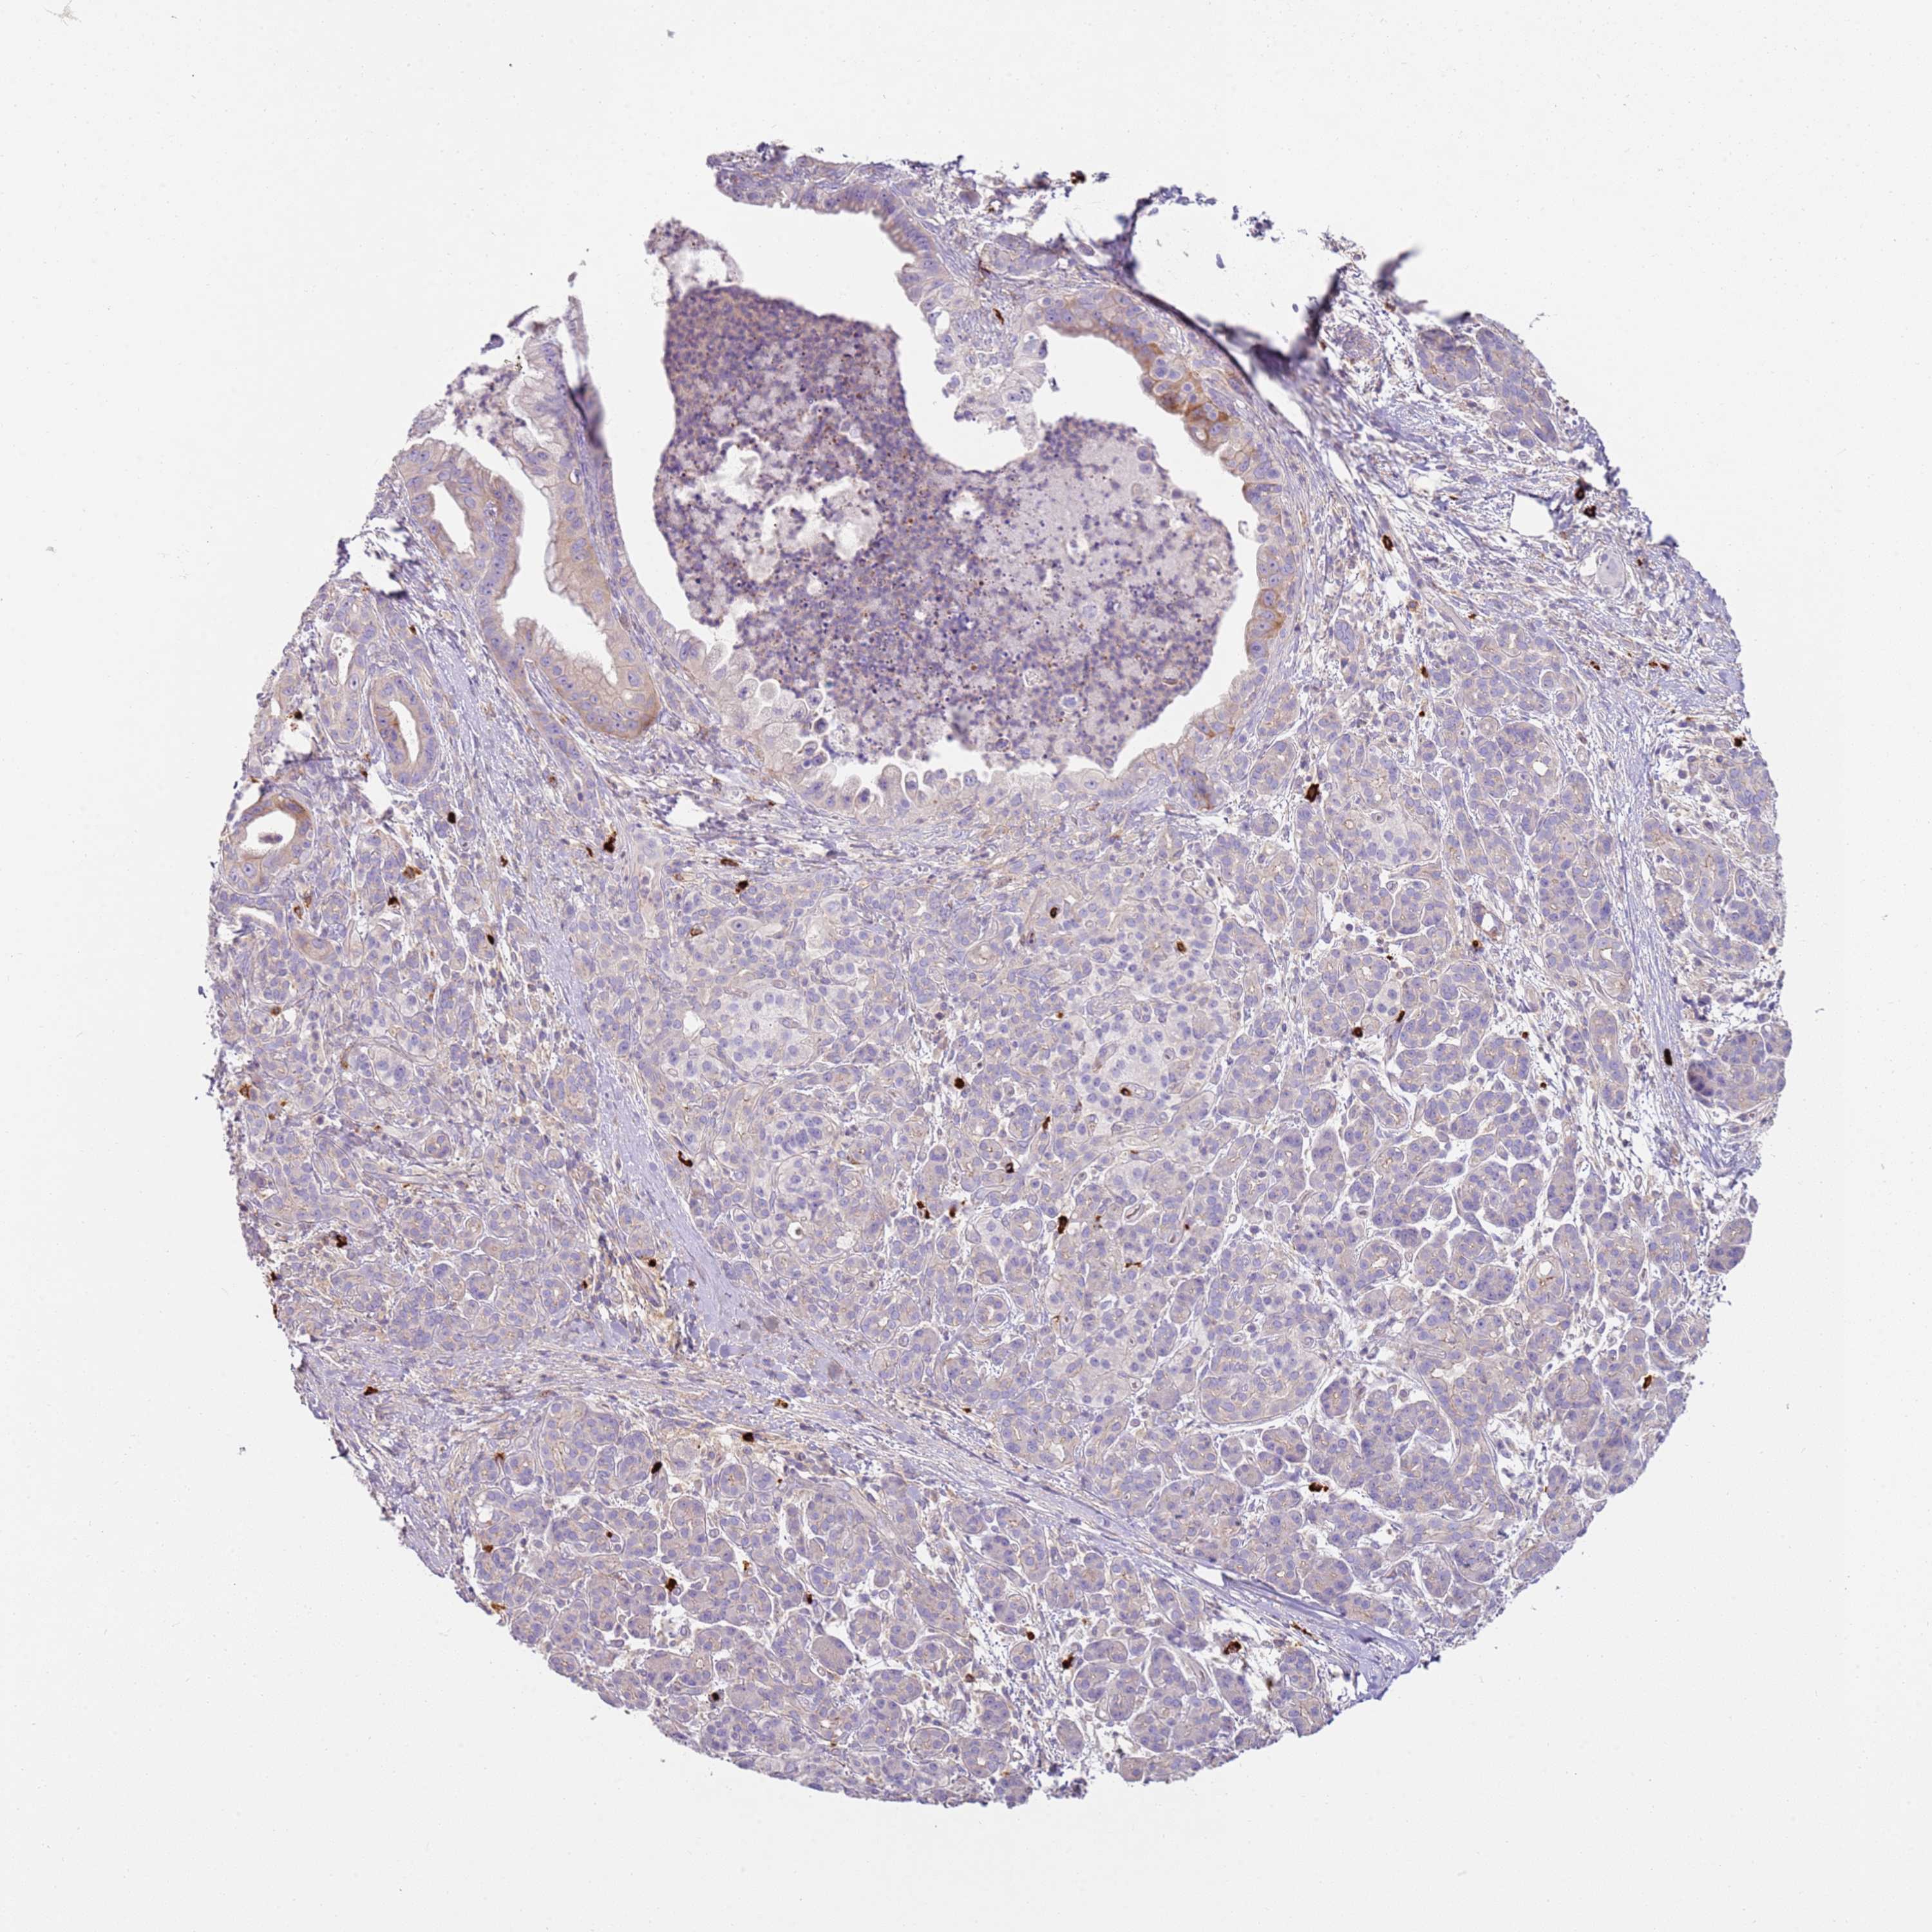

PANCREATIC CANCER - Protein expressioni

A mouse-over function shows sample information and annotation data. Click on an image to view it in a full screen mode. Samples can be filtered based on level of antibody staining by selecting one or several of the following categories: high, medium, low and not detected. The assay and annotation is described here.

Note that samples used for immunohistochemistry by the Human Protein Atlas do not correspond to samples in the TCGA dataset.

Antibody stainingi

Antibody staining in the annotated cell types in the current human tissue is reported as not detected, low, medium, or high, based on conventional immunohistochemistry profiling in selected tissues. This score is based on the combination of the staining intensity and fraction of stained cells.

Each image is clickable and will lead to virtual microscopy that enables deeper exploration of all samples and also displays staining intensity scores, fraction scores and subcellular localization as well as patient and tissue information for each sample.

Antibody HPA046550

Staining

High

Medium

Low

Not detected

Intensity

Strong

Moderate

Weak

Negative

Quantity

>75%

75%-25%

<25%

None

Location

Nuclear

Cytoplasmic/membranous

Cytoplasmic/membranous,nuclear

Adenocarcinoma, NOS